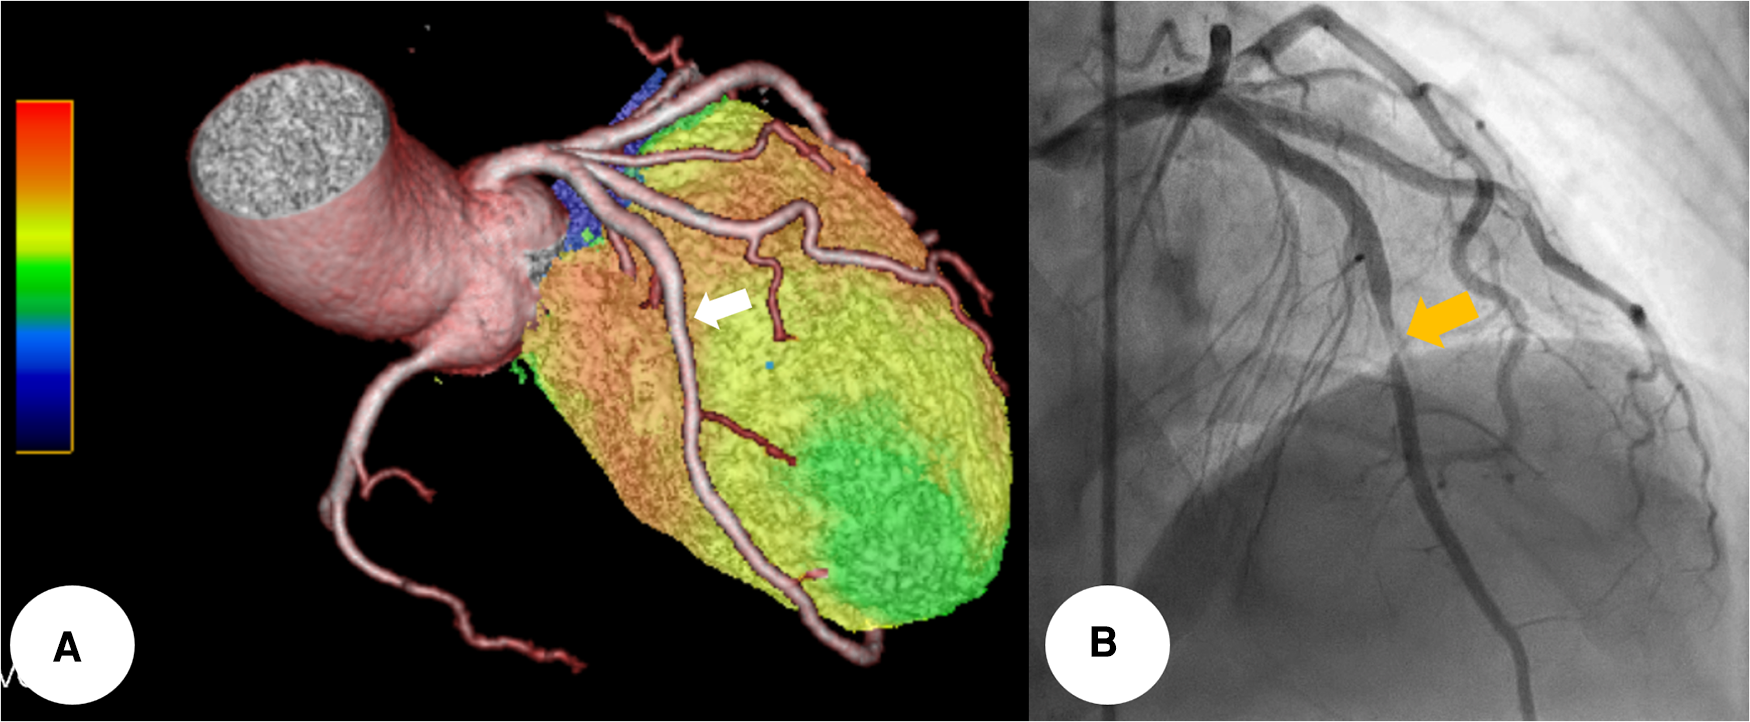

To determine its functional significance, Tc-99 m methylisobutyl isonitrile single photon emission computed tomography (SPECT) was additionally conducted. It demonstrated a medium-sized, moderate fixed perfusion defect around the apex, downstream to the bridging segment of the LAD, suggesting MI (Figure 3). The cardiac SPECT/CCTA hybrid imaging also confirmed excellent correlation between the extent of perfusion defects and the anatomical location of MB (Figure 4A), which was also correlated with CAG finding (Figure 4B).

Figure 4

The cardiac SPECT/CCTA hybrid imaging also confirmed excellent correlation between the extent of perfusion defects and the anatomical location of MB, which was well correlated with CAG finding (whitish arrow and yellowish arrow) (A,B). CCTA, coronary computed tomography angiography; MB, myocardial bridge; SPECT, single photon emission computed tomography.